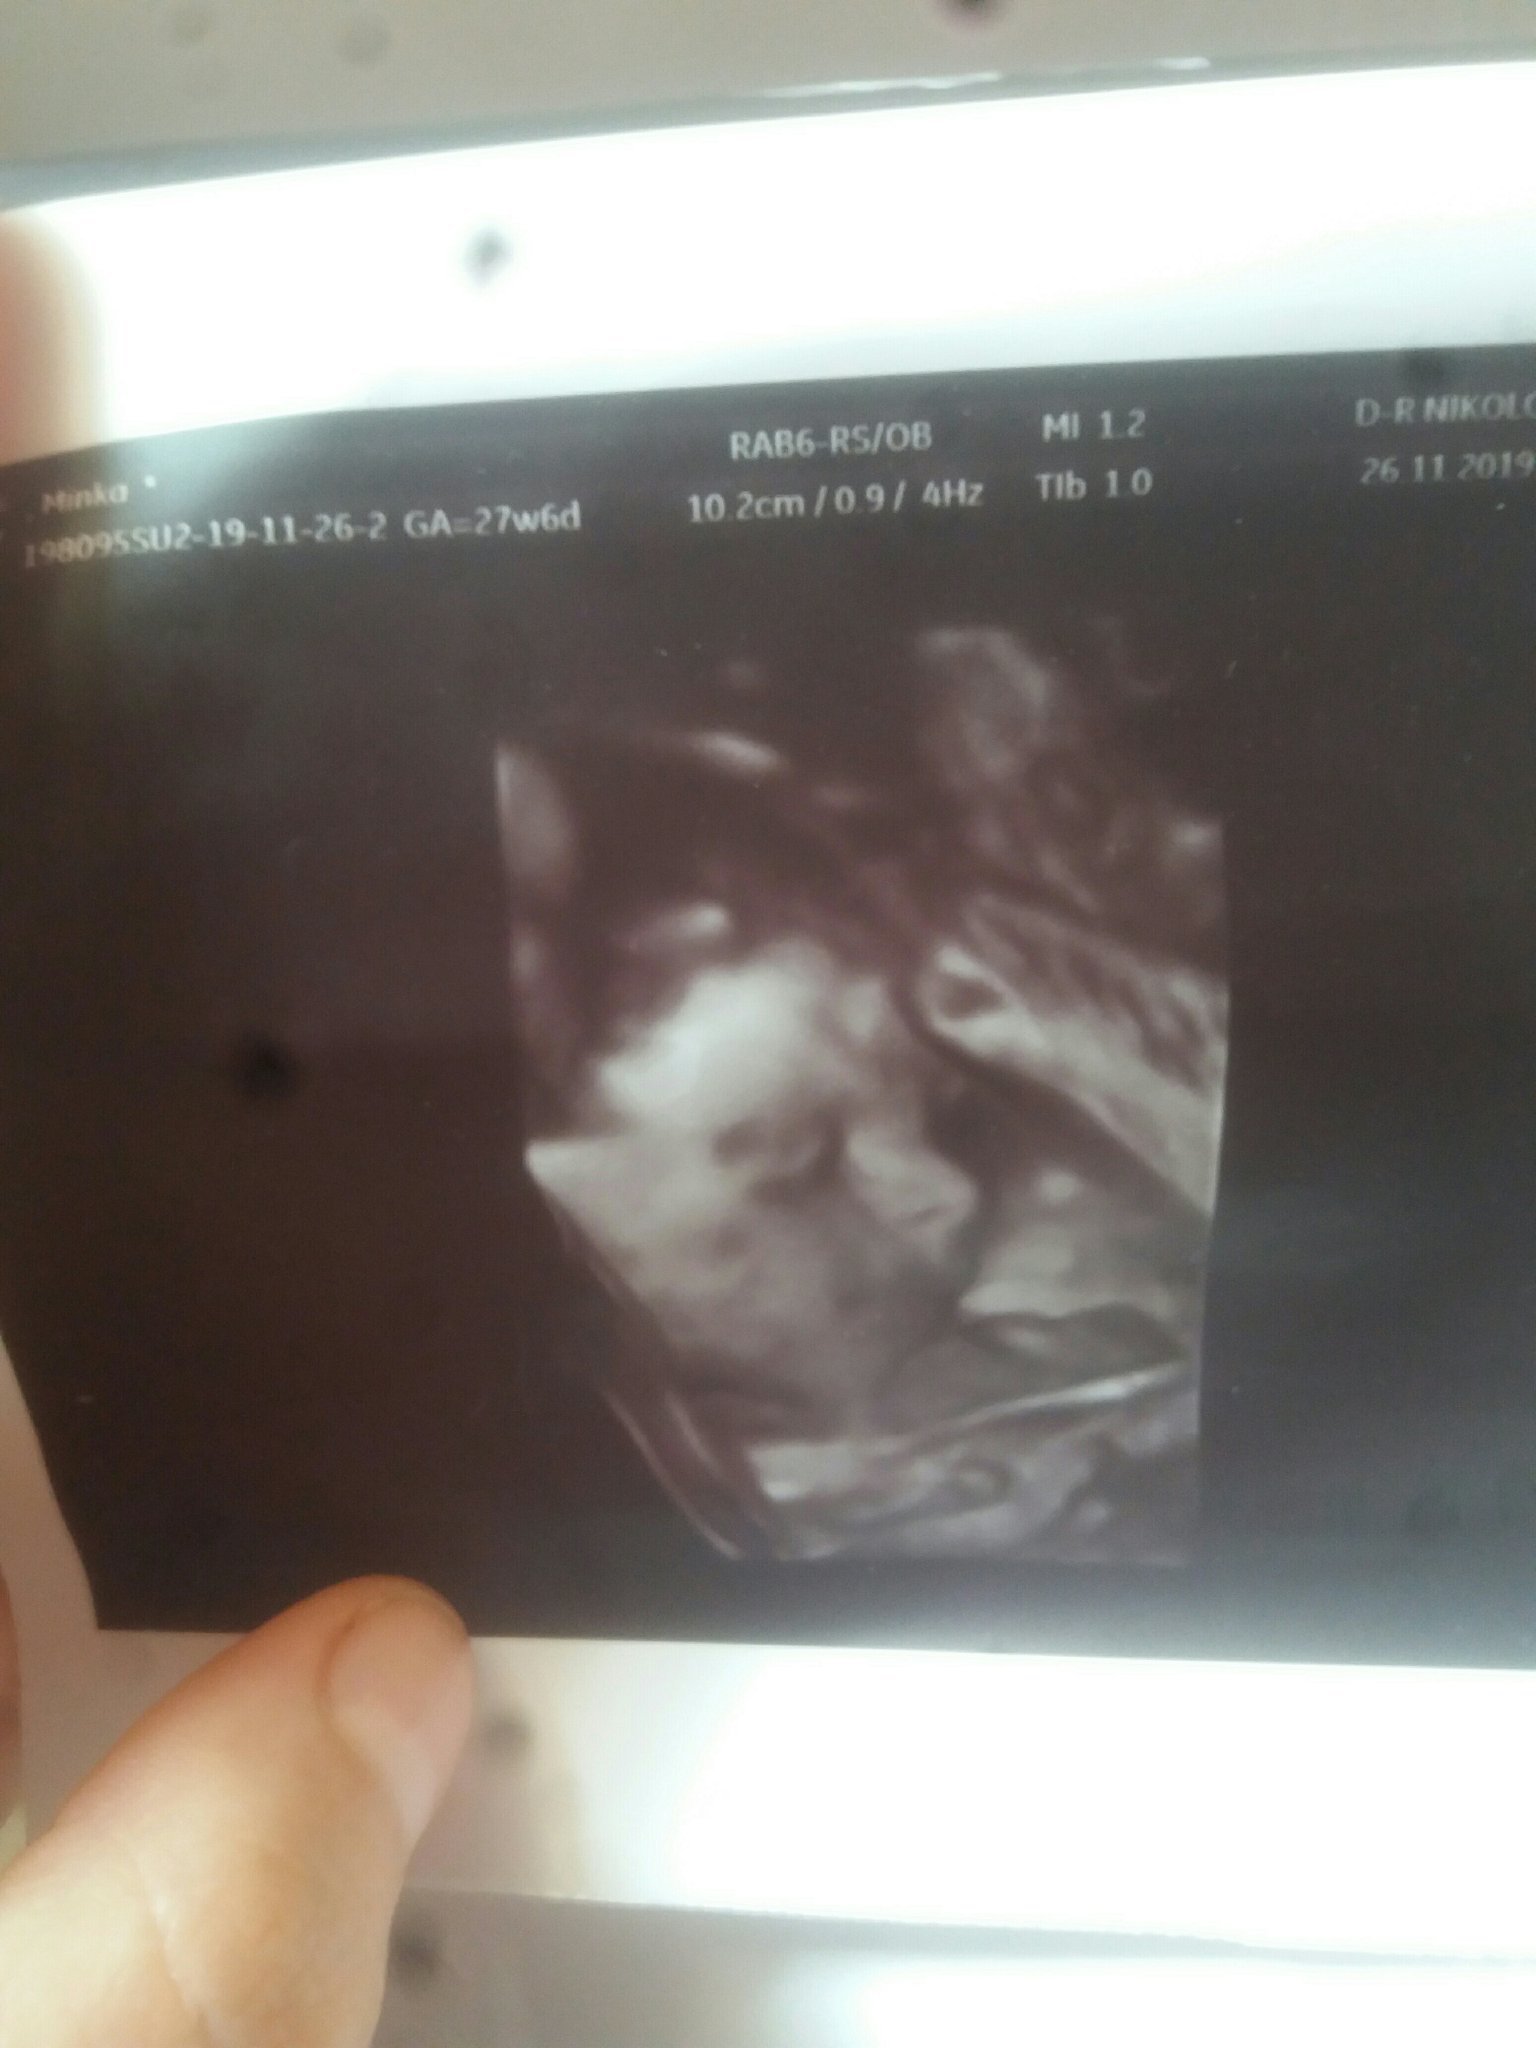

Прегледи по време на бременност включват редовни посещения при гинеколог, където се извършват различни изследвания като ехографски прегледи, кръвни изследвания и тестове за урина. По време на тези прегледи се следи развитието на плода, здравословното състояние на майката и се предприемат необходимите мерки за поддържане на здравето както на бебето, така и на майката. Прегледите по време на бременност също включват измерване на тегло, обиколка на корема, височина на матката, кръвно налягане и наблюдение и изследване с помощта ултразвук за проследяване промените в тялото на бъдещата майка и растежа на бебето. Тези прегледи са от решаващо значение за осигуряване на ценна информация за здравето и нормалното протичане на бременността.